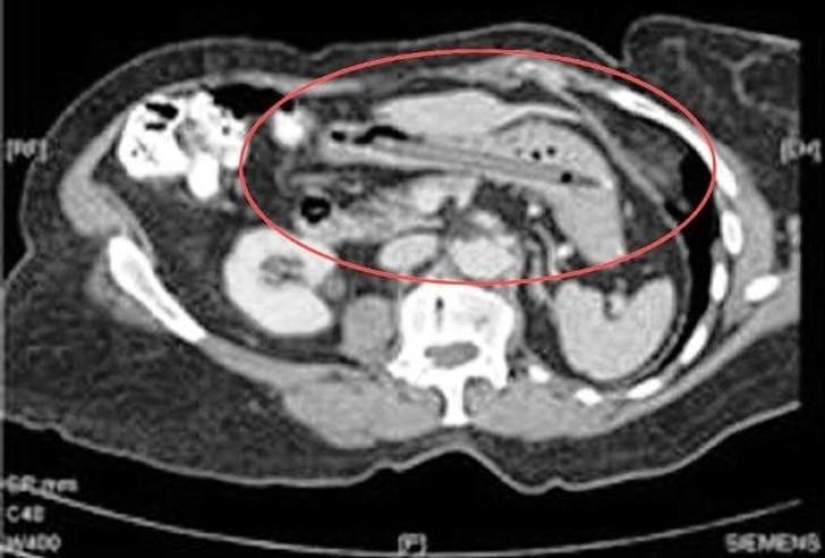

Forceps.